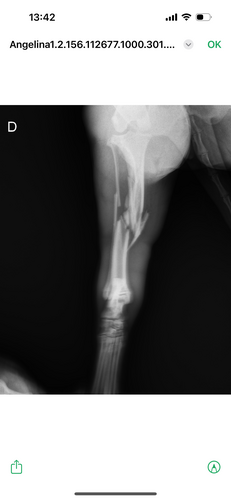

Minha cachorrinha chama Angelina Jolie caiu da laje da minha casa e quebrou a patinha de trás, ela precisa fazer uma cirurgia que custa em torno de 7.000,00. Porém não tenho condições de arcar com o custo sozinha e infelizmente se não fizermos a cirurgia, será necessário amputar a patinha dela 😭. Por favor estou desesperada. Preciso da ajuda de cada um de vocês, pela Angelina Jolie. Desde já agradeço e que Deus lhe dê em dobro.